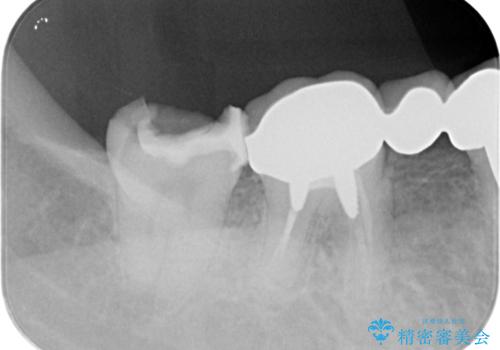

割れたセラミック下に再発した虫歯

- 「以前治療したセラミックが割れ、黒くなっているので診てほしい。」と希望され来院されました。

割れてしまったセラミックインレーの下には大きな虫歯の再発が認められました。

神経を温存するよう、丁寧に虫歯を除去したのち、オールセラミックジルコニアクラウンによる機能回復を行いました。

虫歯は放置すると大きくなり、神経に達していた可能性が高いと思われました。

今回は神経を温存し治療を行うことができました。